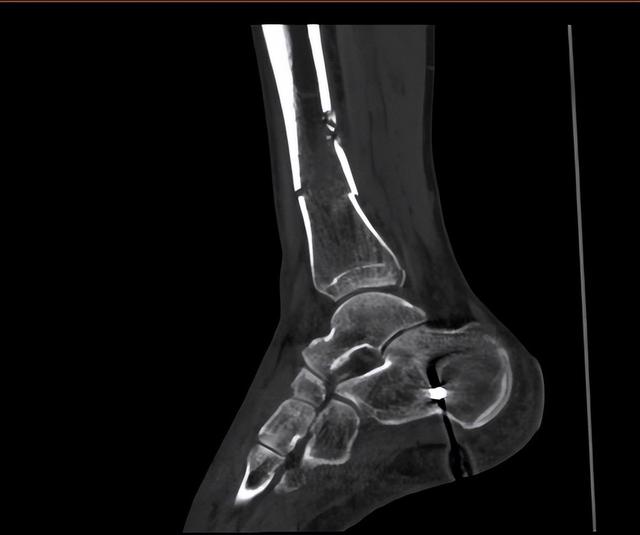

接诊后,我安排患者急查左侧胫腓骨正侧位X片,提示左胫腓骨下段骨折,移位明显,骨块超过2块,上段可见陈旧性骨折。患者病程中无昏迷,无头痛、恶心、呕吐,无呼吸困难,查体肢端暖,左小腿下段肿胀畸形明显,有压痛,踝关节活动明显受限,左足感觉稍麻木。结合患者症状、查体结果和X线表现,确诊患者为左胫腓骨粉碎性骨折。

行车安全要注意:一位39岁男性患者车祸,致左小腿粉碎性骨折-1.jpg

目前患者骨块位置较清晰,但血管位置不甚明确,也可能存在肿胀组织或骨块压迫已破裂动静脉的情况,为避免切开后患者大出血,切开前于左小腿上段扎气囊加压止血带。患者胫腓骨均有骨折,因此需要分开行复位内固定术。术中见骨折呈粉碎型,断端移位明显,清理复位后行内固定,术毕后透视确认位置满意。患者安返病房,术中出血少,取气囊加压止血带,予以加强换药,外用支具保护患处于功能位助愈。嘱患者保护患肢,如术后患处及附近有感觉麻木等不适,及时告知医生。